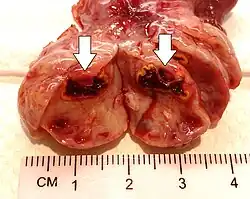

Gross pathology of a corpus luteum cyst with bleeding

This type of functional cyst occurs after an egg has been released from a follicle. The follicle then becomes a secretory gland that is known as the corpus luteum. The ruptured follicle begins producing large quantities of estrogen and progesterone in preparation for conception. If a pregnancy doesn't occur, the corpus luteum usually breaks down and disappears. It may, however, fill with fluid or blood, causing the corpus luteum to expand into a cyst, and stay in the ovary. Usually, this cyst is on only one side, and does not produce any symptoms.[1][2]